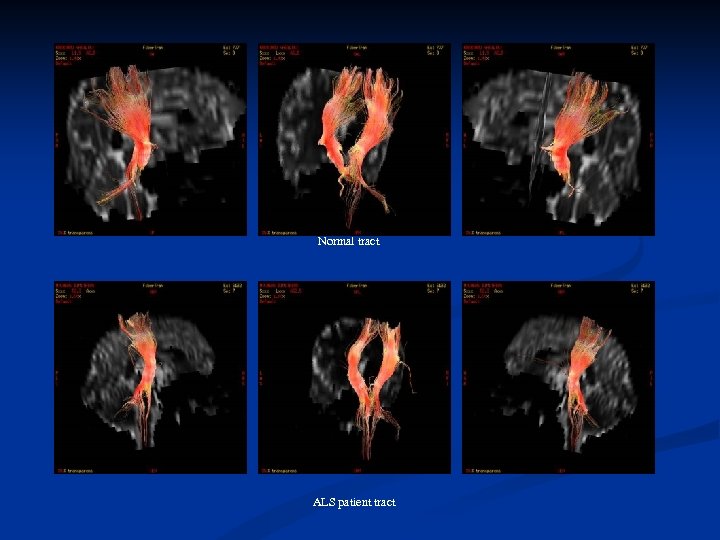

Comparing (FA) measurements, between controls and patients we found that FA measurements in patients were lower than in the age matched healthy subjects. A further decrease in FA measurements was also noticed with disease progression on the F/U study. Using fiber tractography we visualized the CST tract in healthy volunteers as well as ALS patients. A small number of patients, especially those with definite ALS, showed a visibly decreased volume of CST fibre bundles

Comparing (FA) measurements, between controls and patients we found that FA measurements in patients were lower than in the age matched healthy subjects. A further decrease in FA measurements was also noticed with disease progression on the F/U study. Using fiber tractography we visualized the CST tract in healthy volunteers as well as ALS patients. A small number of patients, especially those with definite ALS, showed a visibly decreased volume of CST fibre bundles

Normal tract ALS patient tract

Normal tract ALS patient tract